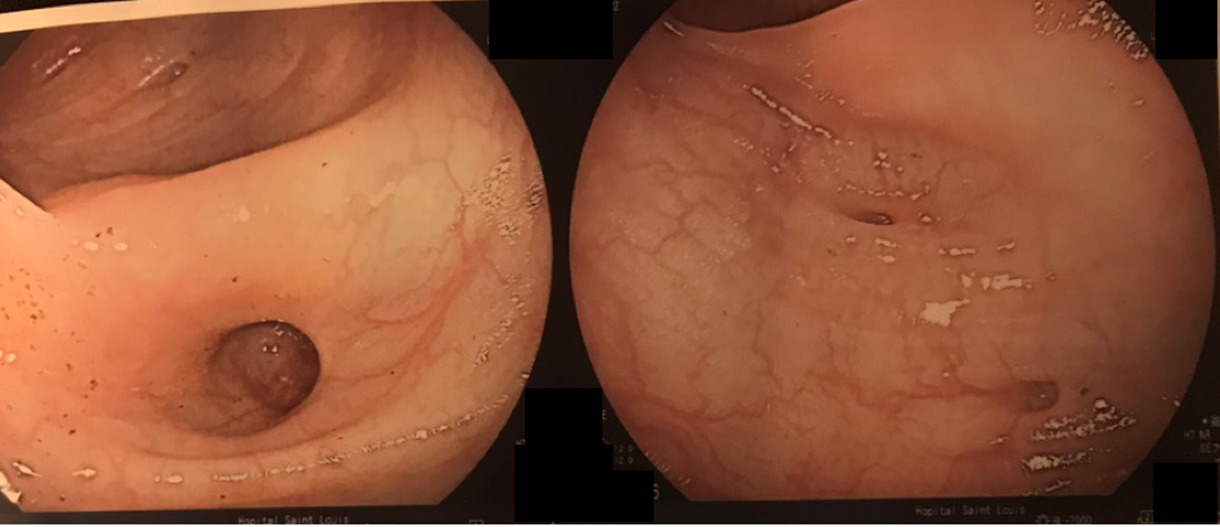

Les hémorroïdes peuvent se manifester de plusieurs façons : par des saignements, par une sensation de boule/gêne au niveau de l’anus et par des douleurs anales à type de cuisson.

Un prolapsus rectal est une extériorisation de la muqueuse rectale à travers l’anus. Il peut entraîner une sensation de gêne au niveau de l’anus de façon intermittente ainsi que des saignements et une incontinence anale.

1. Le traitement de la maladie hémorroïdaire interne qui est constitué de :

– la régulation du transit (le plus important). On prescrit un régime riche en fibres et des laxatifs ;

– un médicament veinotonique en période de crise type diosmine ;

– un traitement topique type suppositoire ou crème qui joue sur une composante anti-inflammatoire permettant de réduire l’œdème local et a un effet antalgique (le plus prescrit est la titanoréïne).